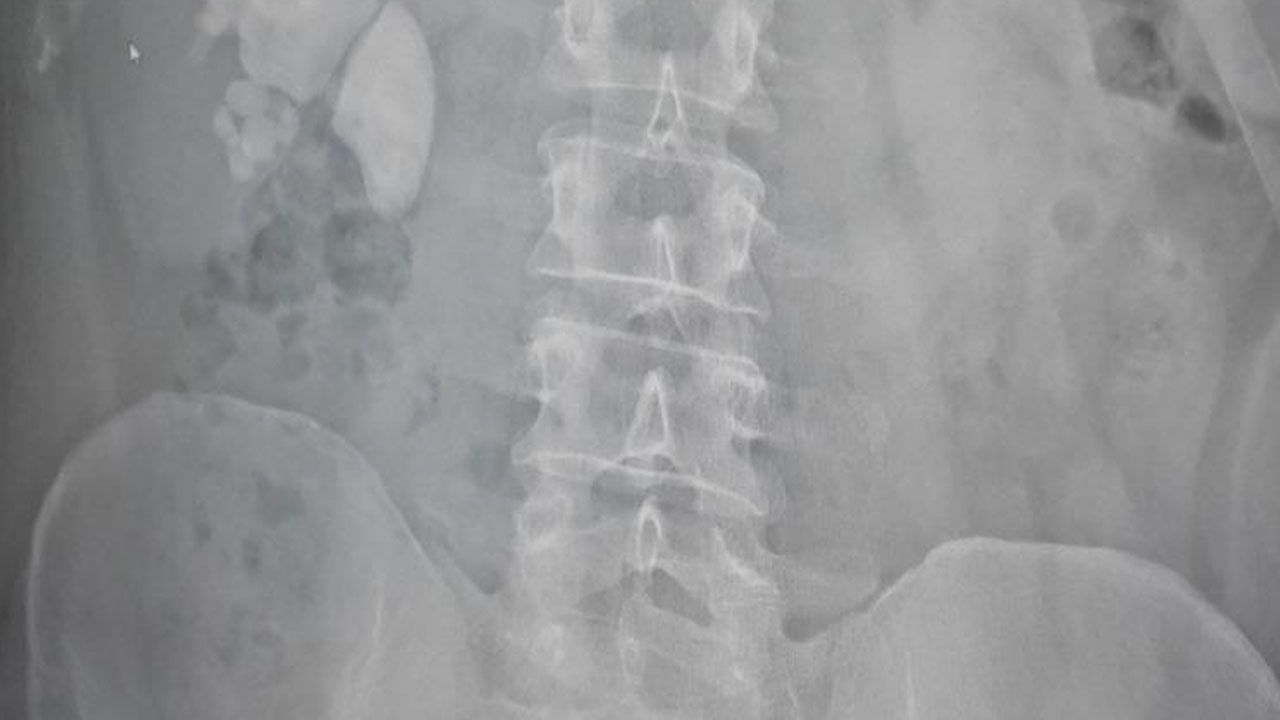

Akdağmadeni ilçesinde yaşayan Serhat Evran doktorları bile şaşırtan sağlık problemiyle karşı karşıya kaldı. Şiddetli böbrek ağrısı şikayetiyle hastaneye başvuran Evran’ın detaylı tetkiklerinin yapılmasının ardından böbreğinde 100 taneye yakın taş tespit edildi.

Hastanın durumu hakkında açıklama yapan Op. Dr. Fatih Kocamanoğlu hastanın 10 yıl kadar önce sağ böbrekten taş cerrahisi operasyonu geçirdiğini ifade etti. Kocamanoğlu, "Yaptığımız incelemede sağ böbreğin tamamını dolduran taşları vardı. Hastayla görüşerek bu tür büyük taşlarda büyük bir cerrahi olabileceğini ve hastanın birkaç delikten girerek, sırttan delerek ameliyat yapılması gerektiğini söyledik. Hastamız kabul etti. Çarşamba günü hastanın ameliyatını yaptık. Tek delikten girerek neredeyse tamamını temizledik. Bugün de hastamızı sağlıklı bir şekilde taburcu edeceğiz" dedi.